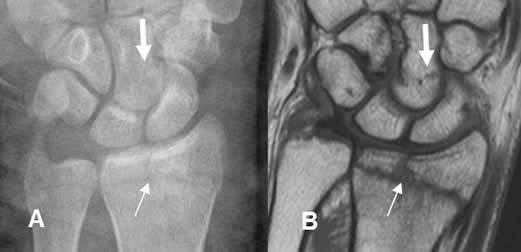

Fig 82. Fractura intra-articular.

A: Rx AP y B: RM coronal en T1. Fractura Salter tipo III, con compromiso intra-articular del radio distal. Adicionalmente hay fractura lineal del hueso grande. (Flecha gruesa).